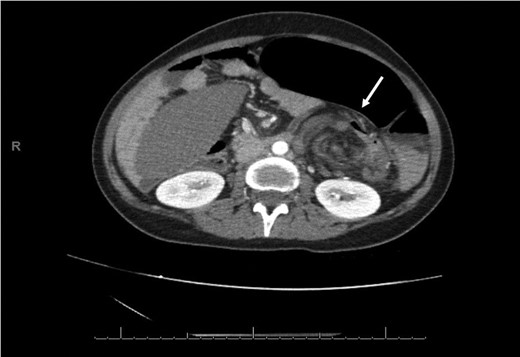

An axial CT of the upper level of the abdomen shows a corkscrew-like soft tissue density (white arrow) indicating twisted splenic vessels surrounded by peritoneal ligaments and fats forming a whirly appearance with alterative lucent and dense bands (a whirl sign), is a pathognomonic CT findings of torsion.

As the diagnosis of torsion of a wandering spleen is challenging, CT scan imaging showing the characteristic sign of a ‘whirled appearance’ of the splenic pedicle is considered the preferred modality for diagnosis of this condition [9].